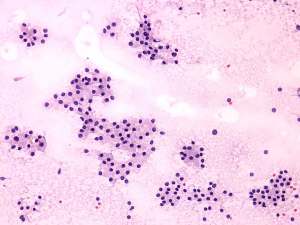

Cytology was performed from the right thyroid. Cytological diagnosis: benign pattern corresponding to hyperthyroidism.TSAb proved to be minimally elevated 2.4 U/mL (normal value below 1.5).